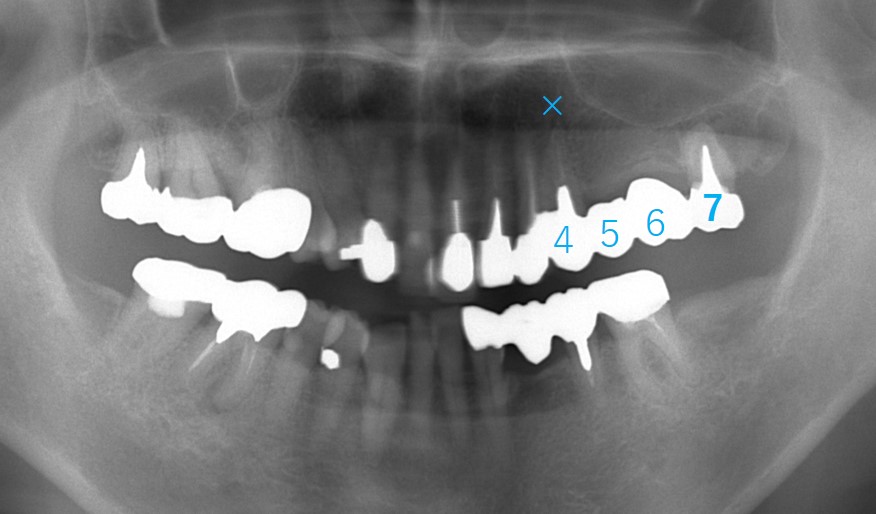

70歳女性です。4番が歯根破折(歯の根が折れる)ため抜歯適応となりました。4、5、6と3本の歯がなくなってしまうためブリッジはできません。また、入れ歯にも抵抗があるためインプラント治療を計画することとしました。

インプラントは、4番と6番に計2本埋入予定。4番は9mmの長さ、6番は上顎洞があるためショートインプラント(6mm)を予定しました。

4番と6番にインプラントを埋入した直後の写真です。

それ後8年経過、現在78歳になられました。

7番は内冠(被せものを2重にして取り外せる)を装着して、インプラントと連結したブリッジになっています。